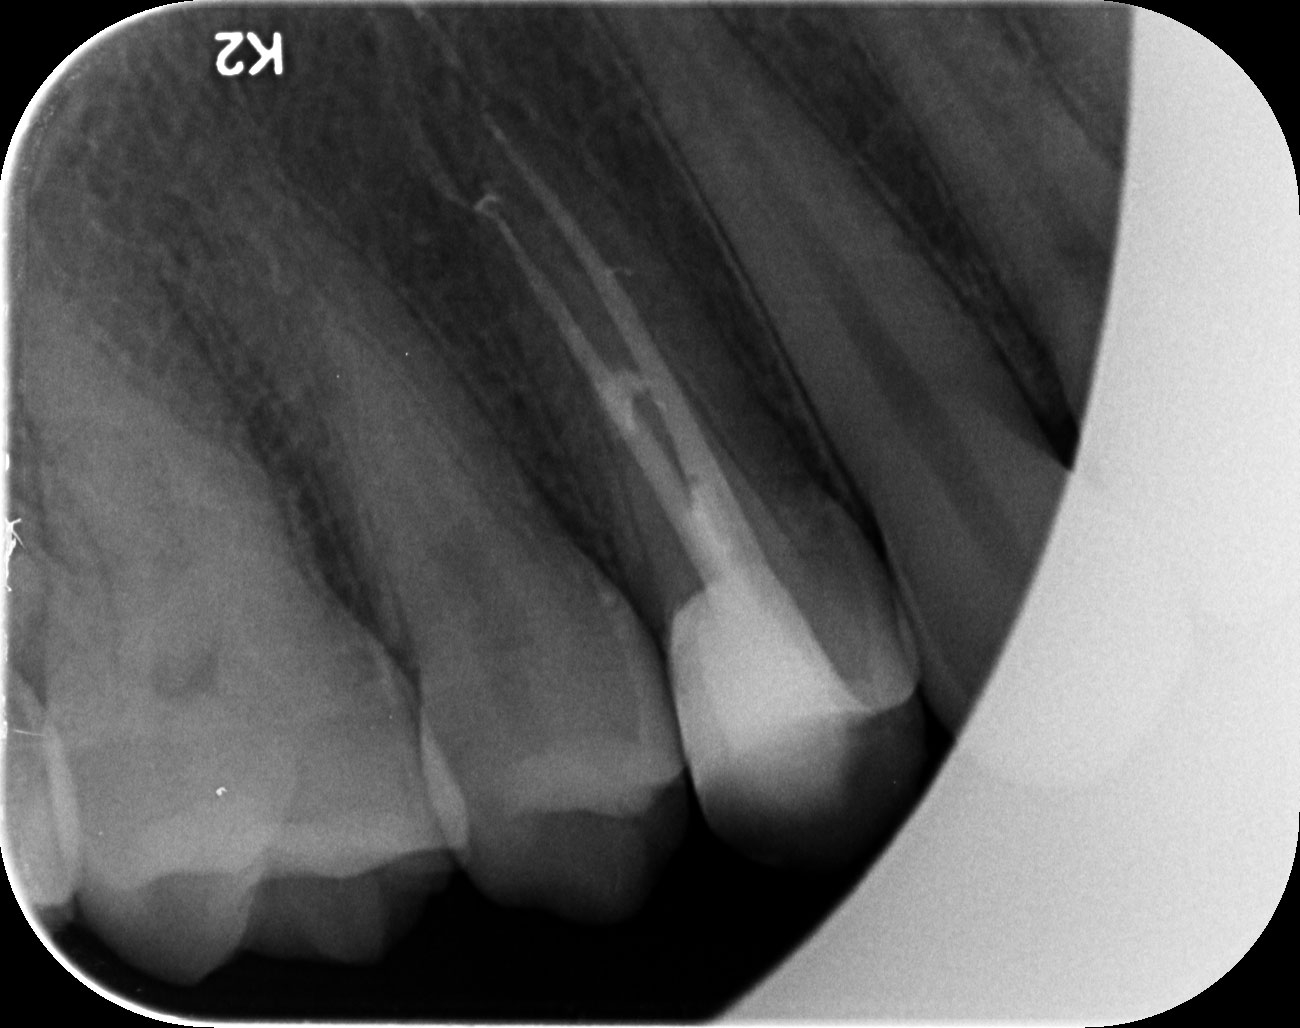

Dantų kanalų gydymas